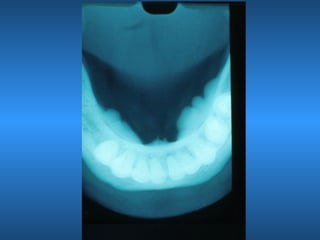

Torus

• Mandibular